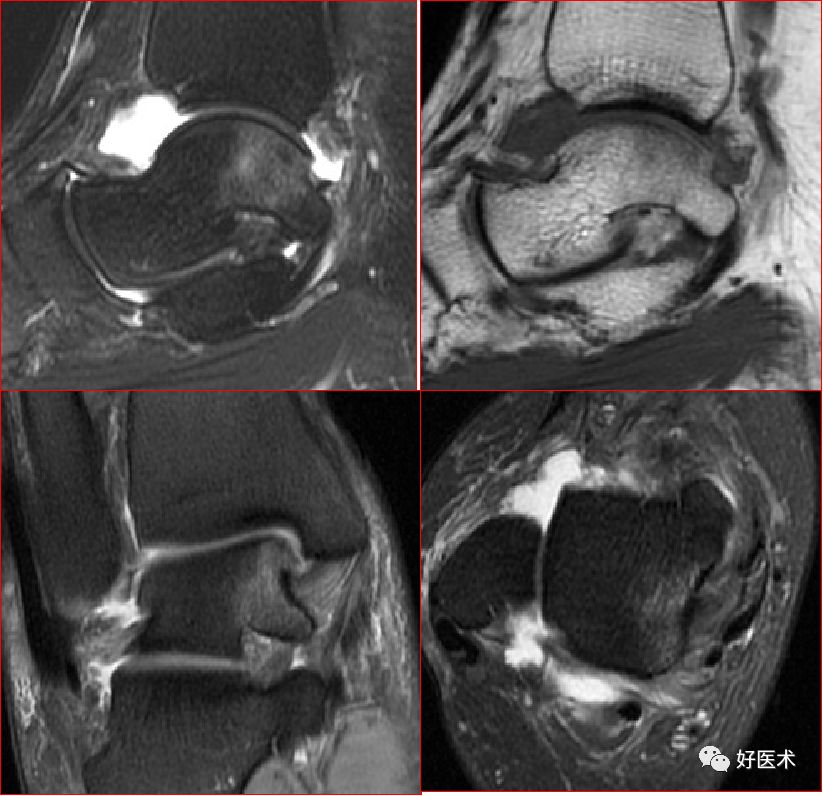

三、骨软骨病变

距骨骨软骨损伤,好发于前外侧、后内侧,尤其是后内侧,与内外翻损伤相关。

距骨骨软骨损伤分级

1度损伤:

2度损伤

3度损伤